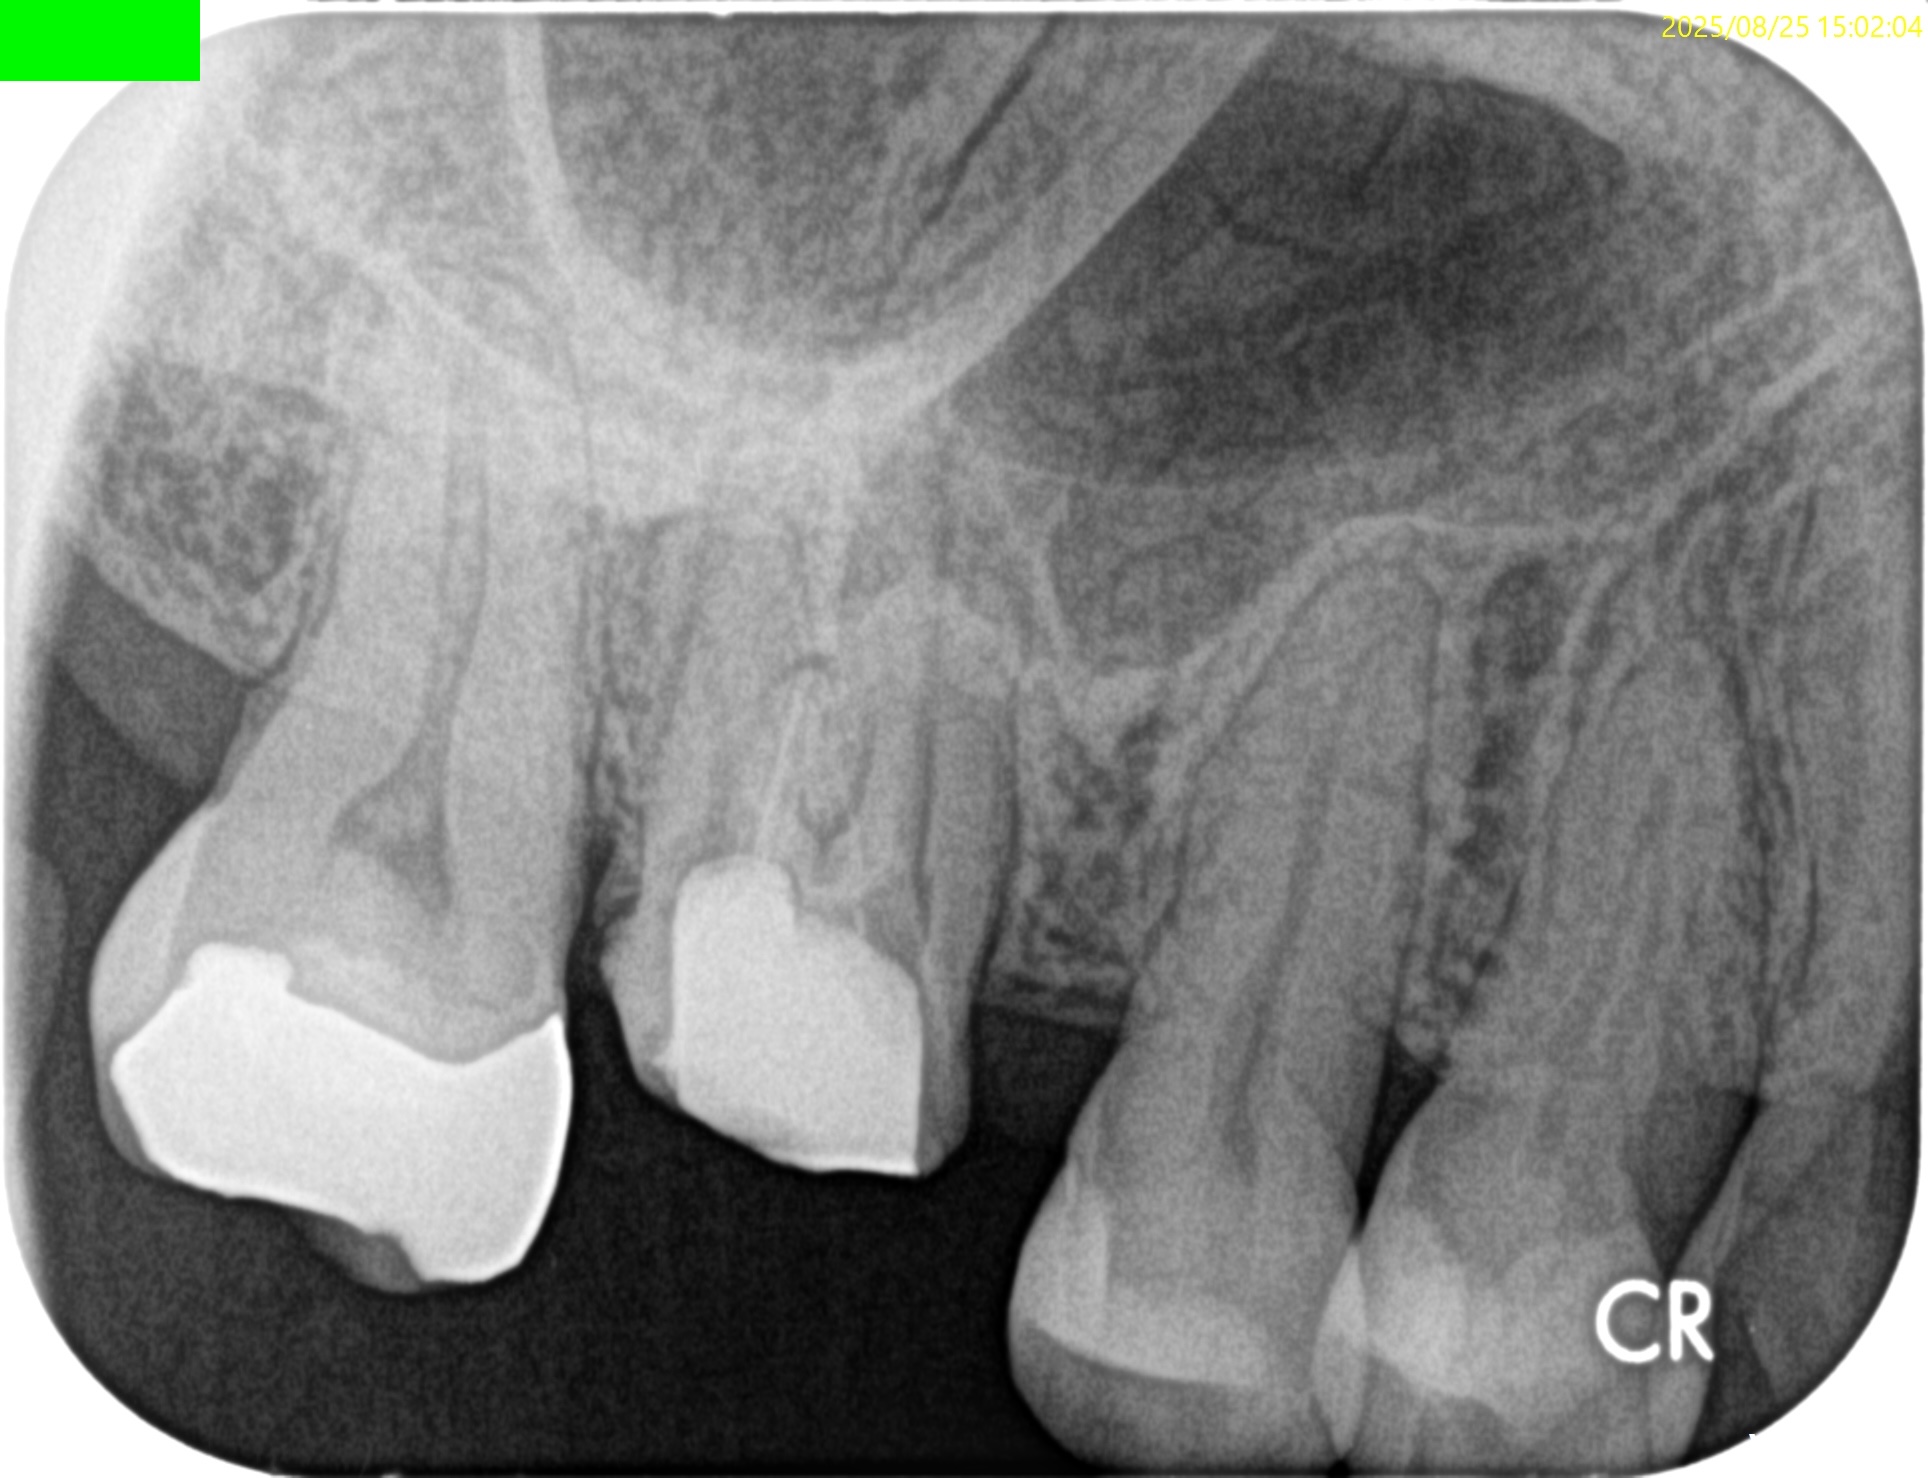

#3 MB, DB Apicoectomy 7M recall(2026.3.30)

MB

DB

P

B

7ヶ月前と比較した。

劇的に歯槽骨の開創は回復している。

そしてP根だが、根尖病変の治癒とともに口蓋側の骨欠損が大きく回復しているのがわかる。

Primary Endo Secondary Perioに見えた

のに、だ。

(歯周ポケットが正常なので歯周病ではないので上記表現は正しい表現とはいえない)

これは単純にエンドだけの問題であったのだ。

そして、

エンドの治療のみでここまで回復していることがこの歯内療法の治療のパワーを示している。

患者さんはSRPなどの歯周治療は一切していない。

HyFlex EDM #60.02でわずか数mm形成しただけなのに、ここまで歯槽骨が回復している。

ともかく、これで最終補綴もOKだ。